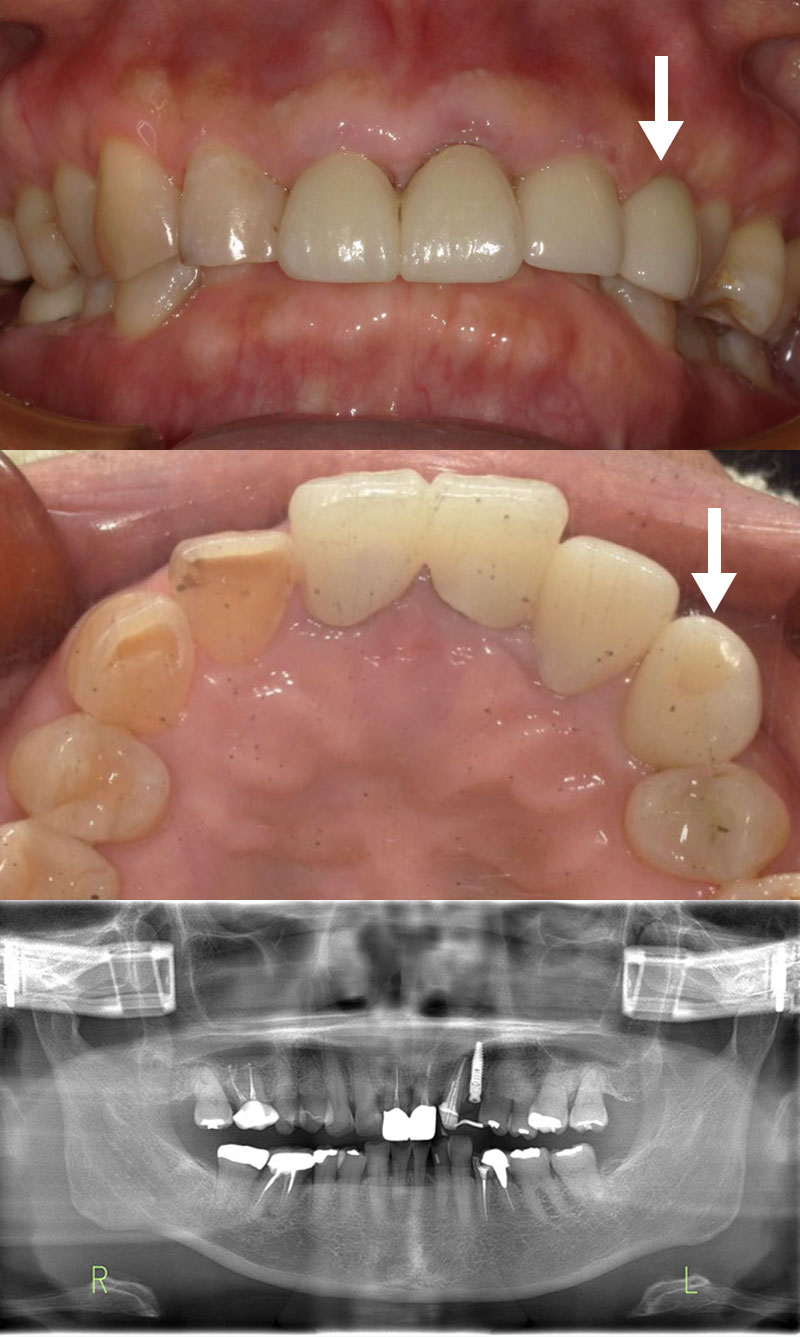

セラミックブリッジによる前歯の審美回復

噛み合わせによって右上2が動揺していた患者さまです。

歯周基本治療を行い経過を観察していましたが、状態の改善が見られず抜歯を決断されました。

治療の選択肢を丁寧にご説明した上で、今回はセラミックブリッジを選択。

抜歯と同時に仮歯を装着し、傷の治癒を待ってからセラミックの型取りを行いました。

また、この患者さまは噛み合わせによって時間破折やすり減りが起こり審美的な面も気にされていましたが、最終的には正常な歯並びに整えることができました。

見た目の自然さとしっかり噛める機能を両立し、大変ご満足いただいています。

| 患者様 | 50代男性 |

|---|---|

| 主訴 | 前歯が欠けた |

| 治療費 | ジルコニアセラミック費用:1歯132,000円(税込) ジルコニアブリッジ6歯総費用:726,000円(税込) |

| 治療期間 | 2ヶ月 通院回数:約5回 |